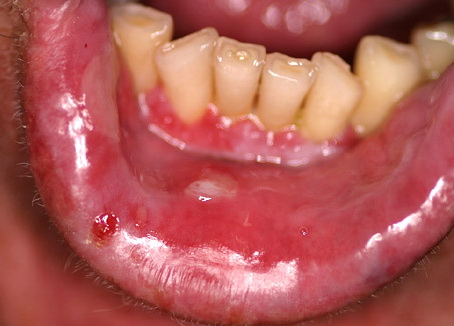

Pemphigus vegetans = الفقاع المتنبت